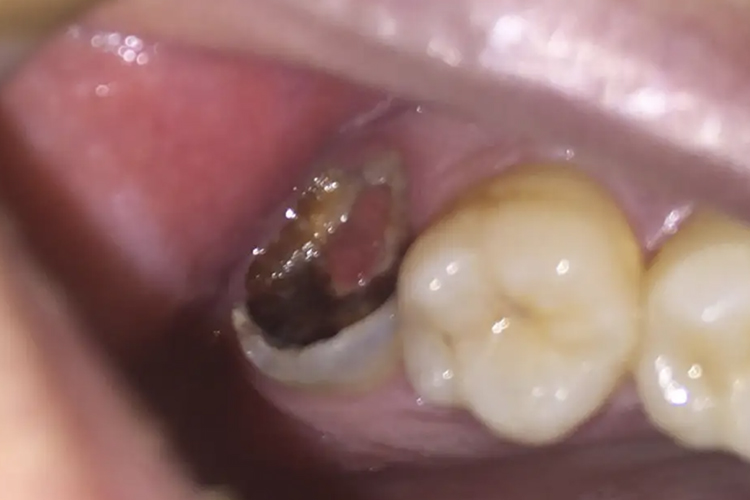

牙龈息肉多是在患牙邻面出现龋洞时,由于食物长期嵌塞加之患牙龋损处粗糙边缘的刺激, 牙龈乳头向龋洞所形成的空间增生,形成息肉样肉芽组织,导致牙龈息肉。

牙龈息肉在临床上一般采取牙龈息肉切除术,即自蒂部将息肉切除,以达到较好的预后。若局部已经有明显炎症,需遵医嘱使用抗生素治疗,如头孢美唑、甲硝唑等。若突然破损出血严重,需咬合干净的棉球进行压迫止血。

同时需积极治疗龋病,可磨除已经龋坏的部分后进行填充修补。若伴随根尖周炎,需进行根管治疗。若牙体龋坏严重,可进行牙冠修复。